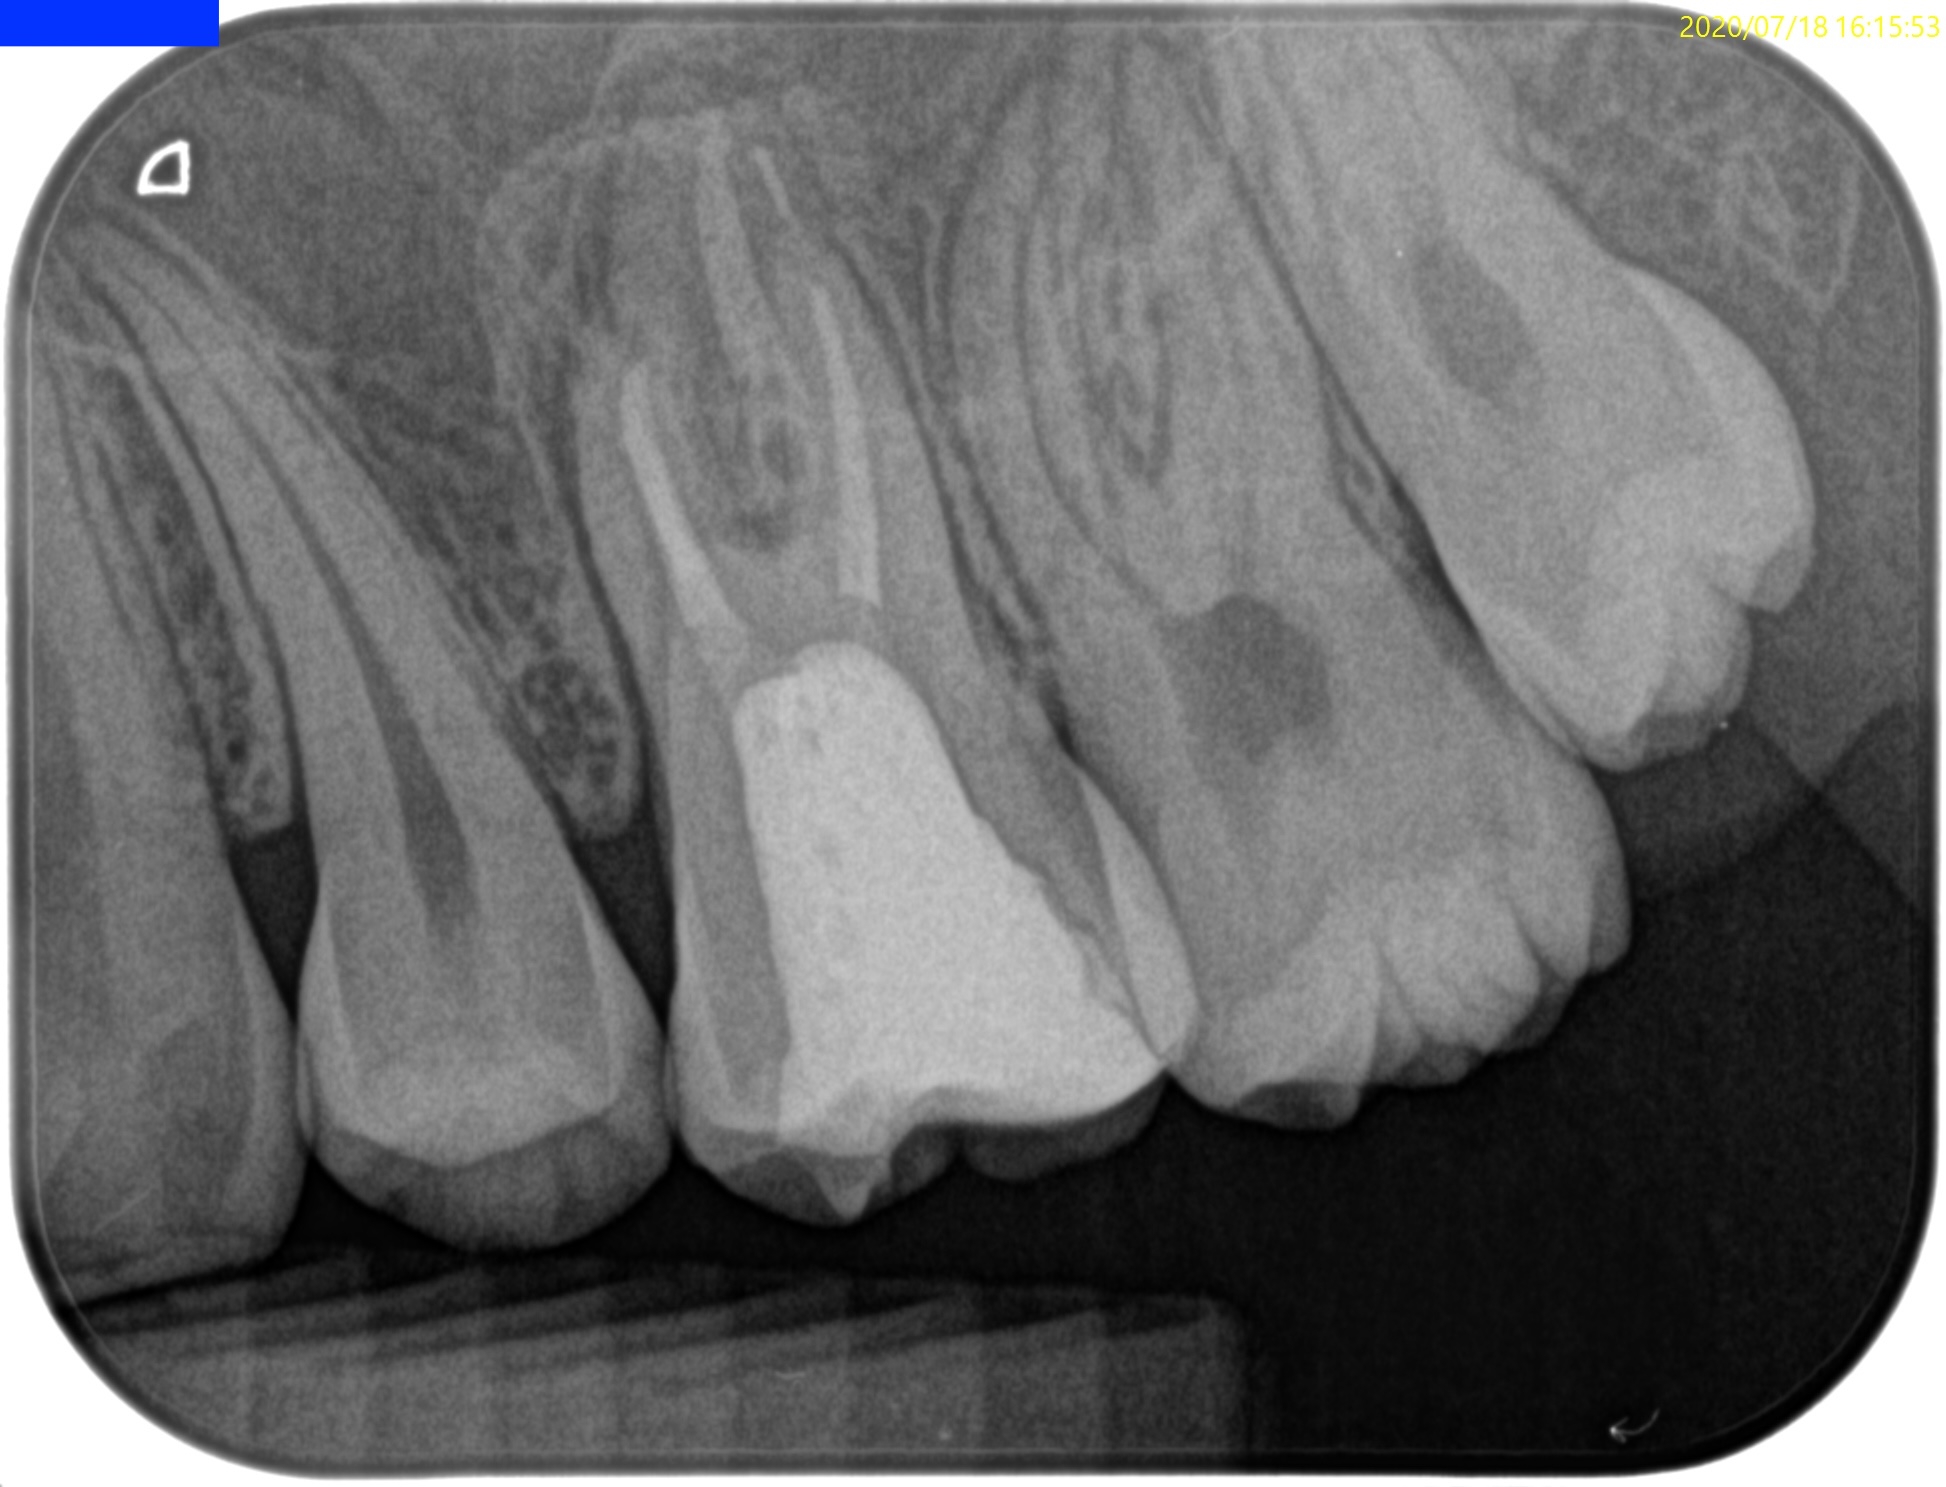

#14 Re-RCT(2020.7.18)

#14 Re-RCT 6yr recall(2026.1.27)

MB

MB2

DB

P

根尖病変は消失した。

また、再治療直後に根尖孔外へとはみ出たGutta Percha Pointの残渣も消失した。

マイクロファージに貪食されたのか?それは神のみぞ知る話だ。

ということで、この日で終診とさせていただいた。